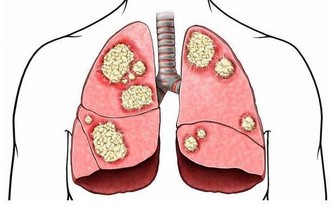

我們大家都知道,在我們呼吸的空氣當中有許多的雜質,比如灰塵、沙塵等等,鼻毛就像是一道屏障一樣,

鼻毛能夠有效過濾外界的雜質,防止灰塵進入到我們的身體當中,損傷我們的肺部健康,這一點是保護肺臟的作用。我們的身體離不開呼吸,24小時裡鼻腔都在進行工作,